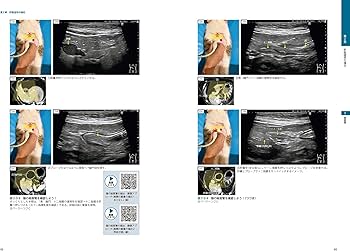

※裁断済みです。自炊にしか使用していませんが、猫を飼育している環境での使用と、裁断済みのため〈状態が悪い〉に設定しております。犬と猫の腹部超音波に関するビジュアルガイド、114ページの詳細な解説付き。- タイトル: 犬と猫の腹部超音波の描出レッスン 下巻- 著者: 戸島鷹史- ジャンル: 健康・医学- 内容: 腹部超音波に関するビジュアルガイド- ページ数: 114ページ- 付属情報: 動画リンク付き- 形式: 書籍ご覧いただきありがとうございます。即購入可です。値引きは基本的には考えておりません。